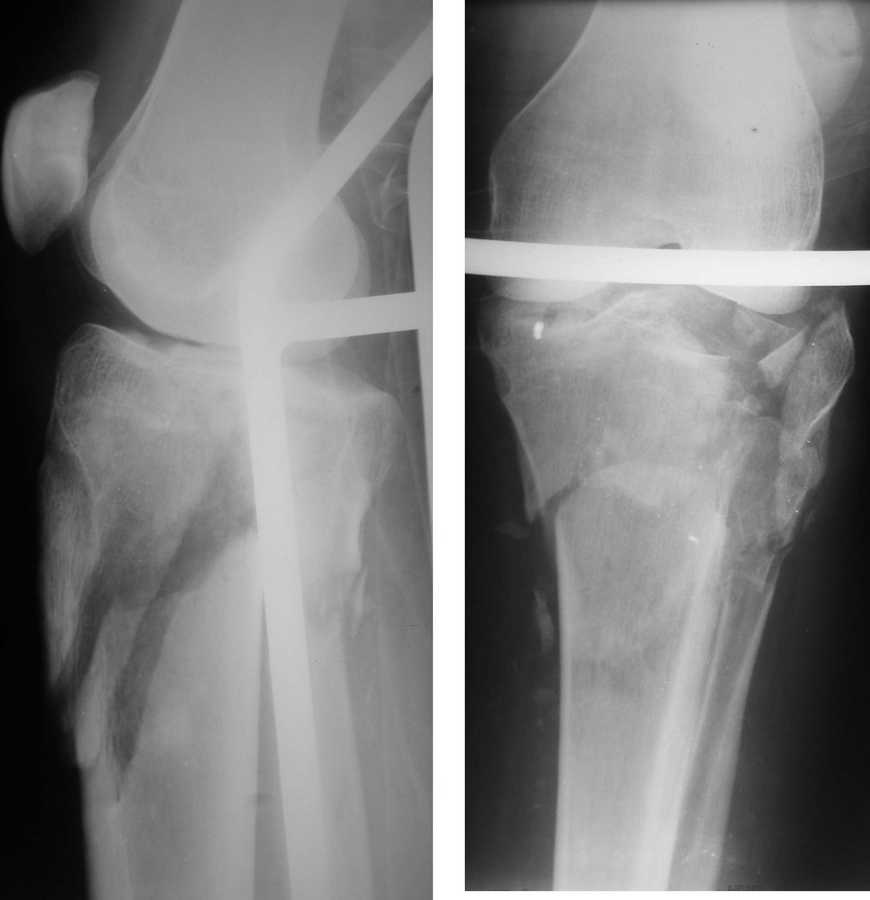

Приветствую всех. Вот такой перелом - неделю назад. Лет 25.

Открытый раздробленный перелом проксимального отдела большеберцовой кости. Имеется рана, ушитая, и заживающие фликтены (со слов родственников). Скелетное вытяжение.